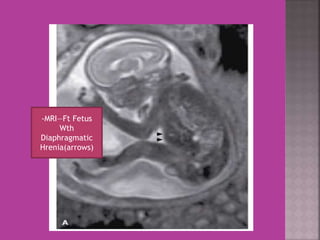

-MRI—Ft Fetus

Wth

Diaphragmatic

Hrenia(arrows)

-MRI—Ft Fetus Wth Diaphragmatic Hrenia(arrows)